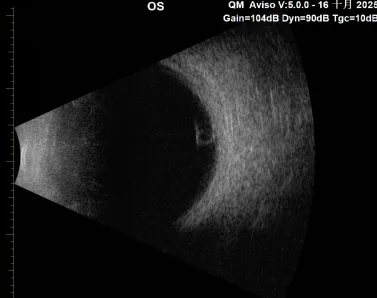

B超:左眼玻璃体内与视网膜间的圆形中等回声。